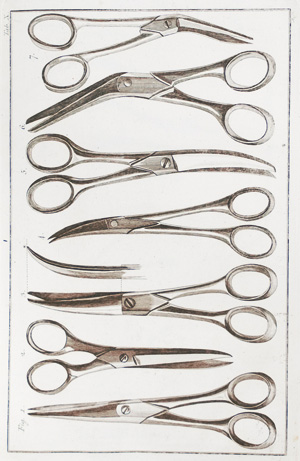

Ebermaier, Johann Erdwin Christoph

Taschenbuch der Chirurgie

Nachverkaufspreis

100€ (US$ 114)